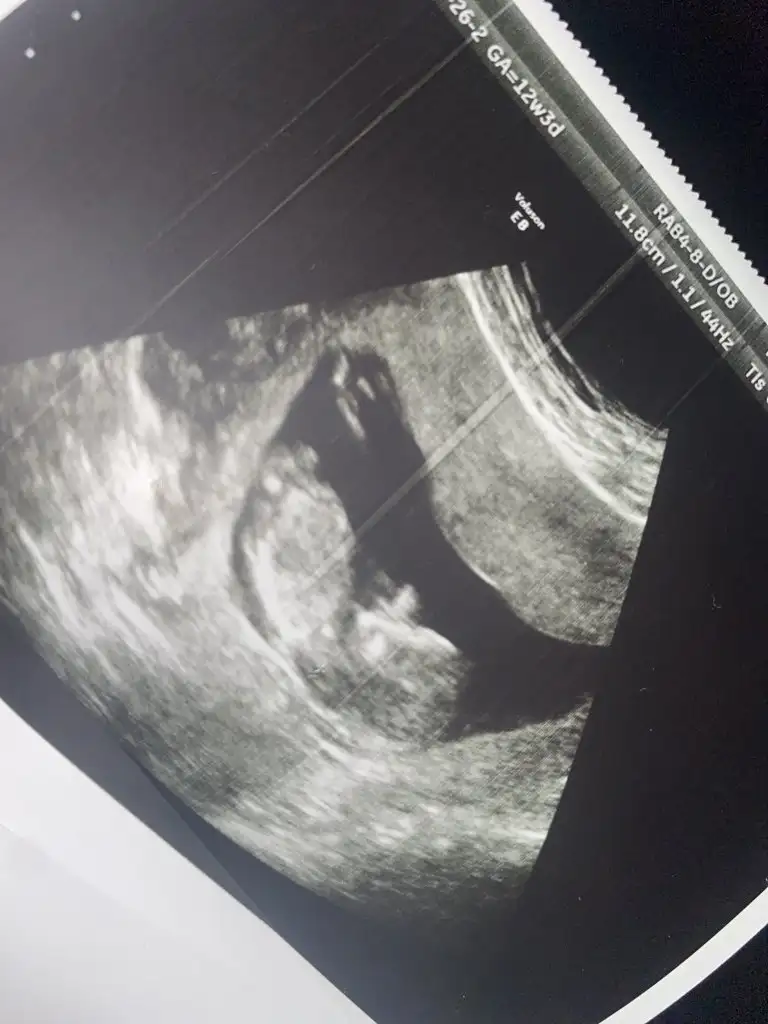

Evet erken en iyi 11 12 13 haftalar olmalı USG 9 haftalık sanırım.Bir yorumda ben alabilir miyimBiraz erken ama

11 12 13 haftalar olmalı9+2 rica etsem tahmin yürütür müsünüz?Ikra meyra

Nub çok minik duruyor sanki kız gibi emin olamadım başka usgde paylaşın teyit edelim

Nubu tam karşıya bakiyor bu durumda % 60 yanılma olur şimdilik kız gibi gibi diyorumÇektim